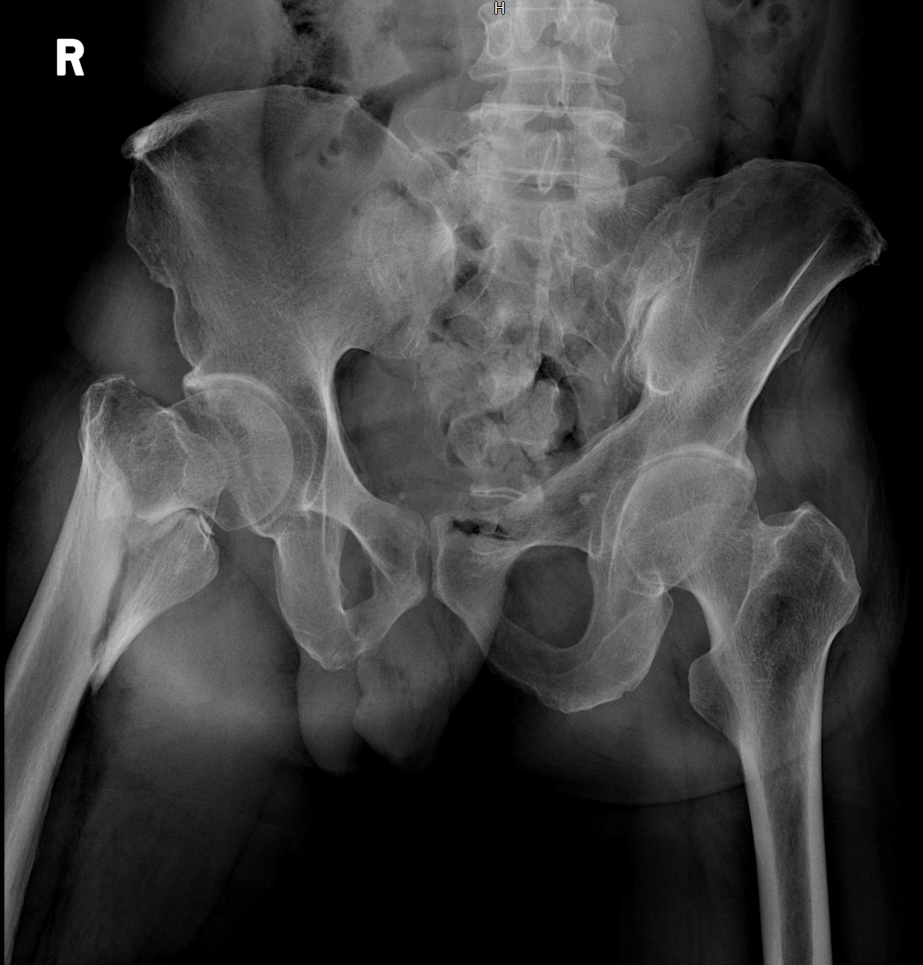

5.辅助检查:我院骨盆CT示:右侧股骨颈及转子间骨折。

术前影像学检查: